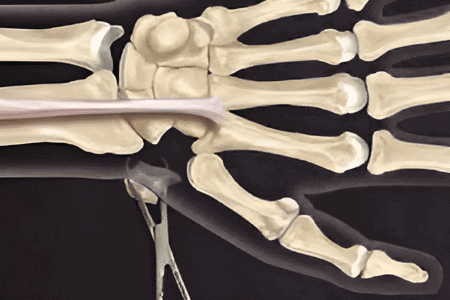

- Dislocations: This happens when the bones in the hand or wrist are displaced, often caused by direct impact or falls.

- Ligament tears: Tears in the ligaments, such as the thumb ligament (gamekeeper’s thumb), can impair hand function and require medical attention.

4. Joint realignment (Open reduction)

- Procedure: Dislocated joints are surgically repositioned and stabilized to prevent recurrence.

- Ideal for: Severe or recurrent dislocations, especially in the fingers or wrist.

- Benefits: Prevents joint instability and reduces the risk of future injuries.